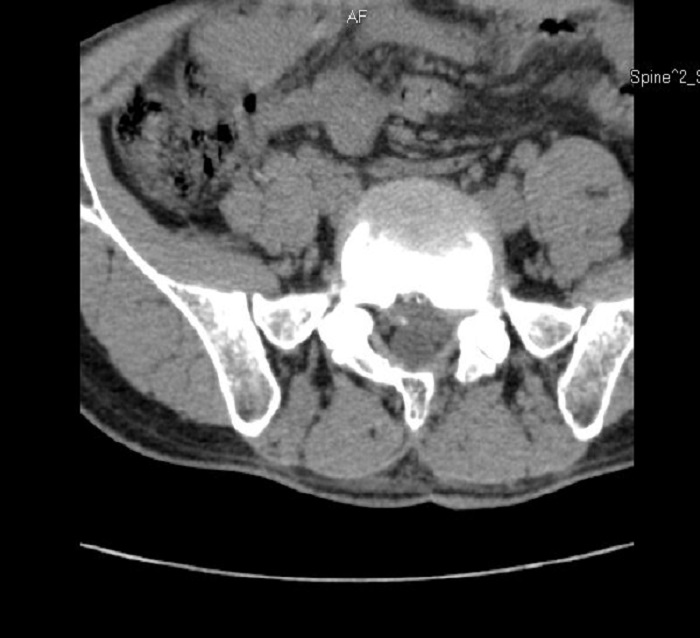

术后